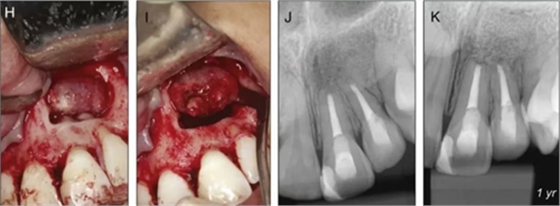

圖5. 翻瓣后將根尖區(qū)病理組織及21、22根尖完整切除,切除組織立即置于10%福爾馬林中固定。牙根倒預備、充填,植骨蓋膜。

圖6. 病例組織大體圖及X線片